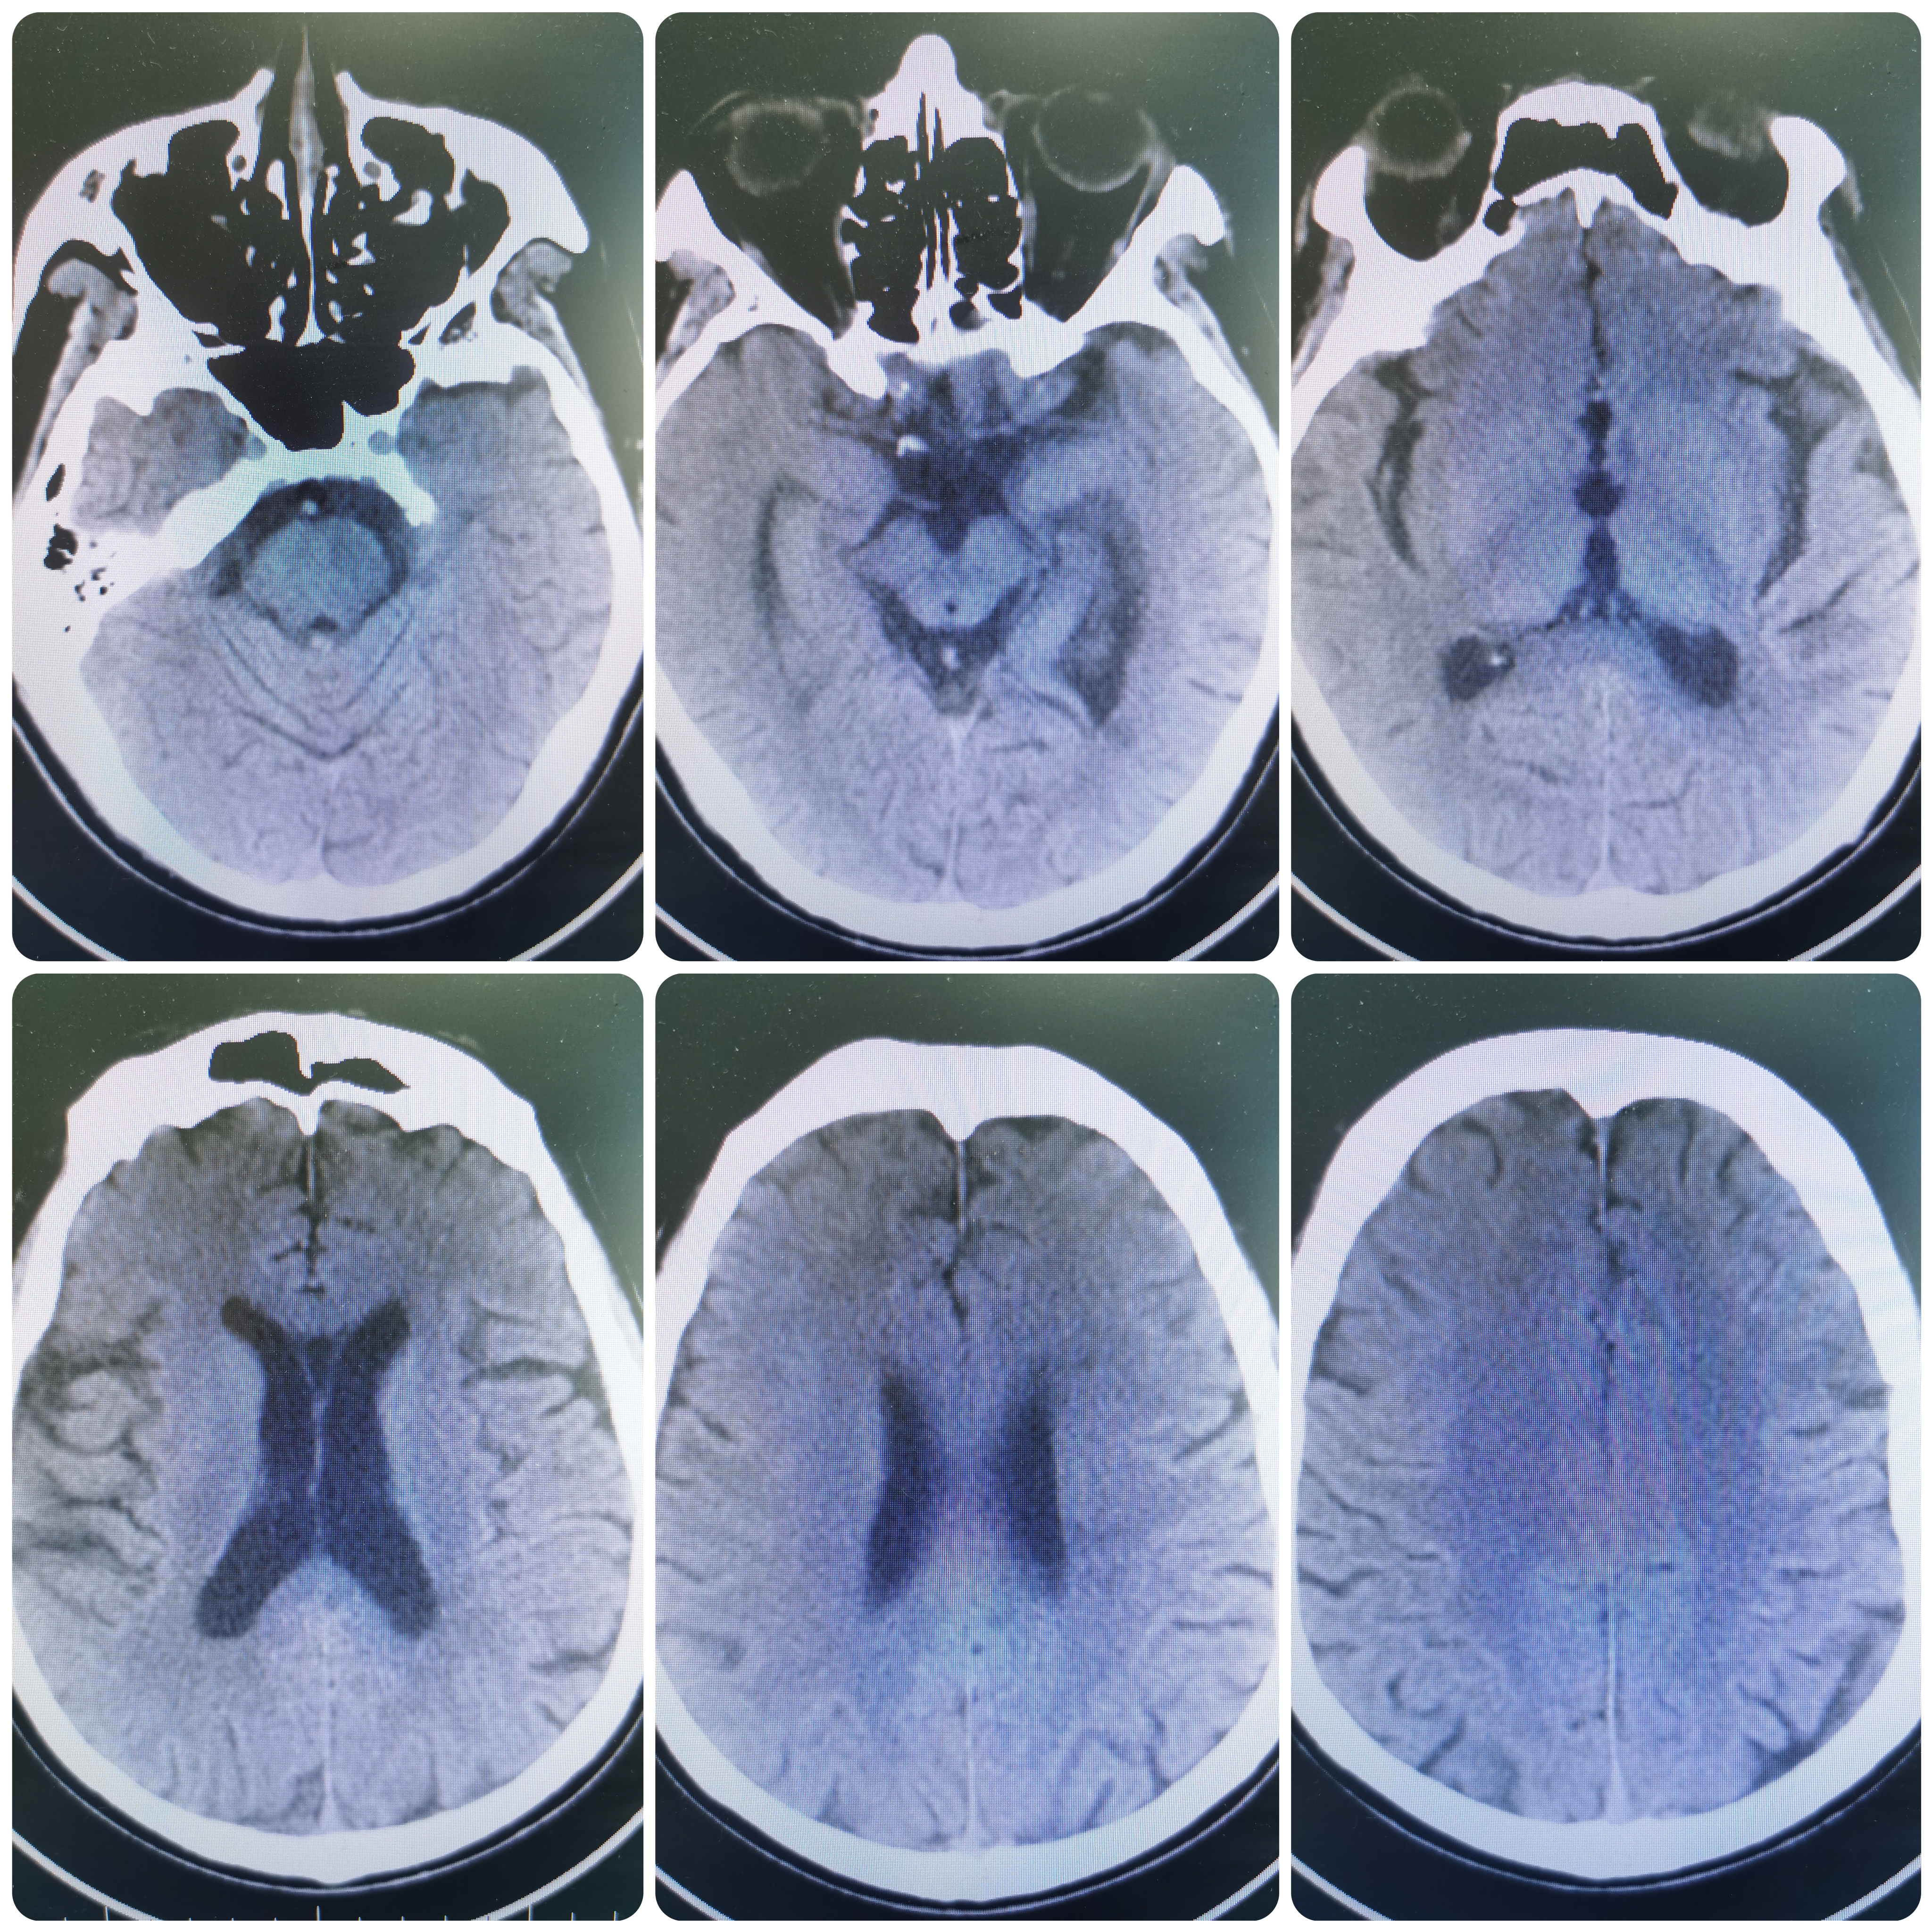

患者MQ,男性,61岁,因言语含糊,右侧肢体麻木无力1周入院,既往高血压病,糖尿病病史多年。

头颅CT示颅内多发梗死灶。

核磁DWI示左侧脑室后角及左侧侧脑室旁新发脑梗死。

1、脑梗死

2、左侧大脑中动脉闭塞

3、高血压病2级

4、糖尿病